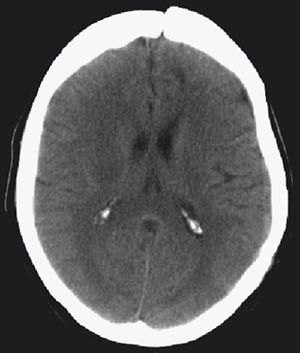

Det postoperative forløpet var ukomplisert. En uke postoperativt hadde pasienten ikke lenger afasi, og hemiparesen var gått betydelig tilbake. Tre uker postoperativt hadde hun normal nevrologisk status. Cerebral CT en måned postoperativt viste betydelig tilbakegang av ødem (fig 3). Fire måneder postoperativt ble beinlappen lagt tilbake, og cerebral CT viste minimale lavattenuerende forandringer frontalt på venstre side (fig 4).